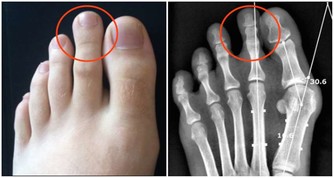

橫向刷牙會損傷牙釉質,同時也會刺激牙齦。牙頸部的釉質很薄,如果長時間的橫向刷牙會造成牙頸部嚴重磨損,形成牙齒楔狀缺損。

(稧狀缺損)